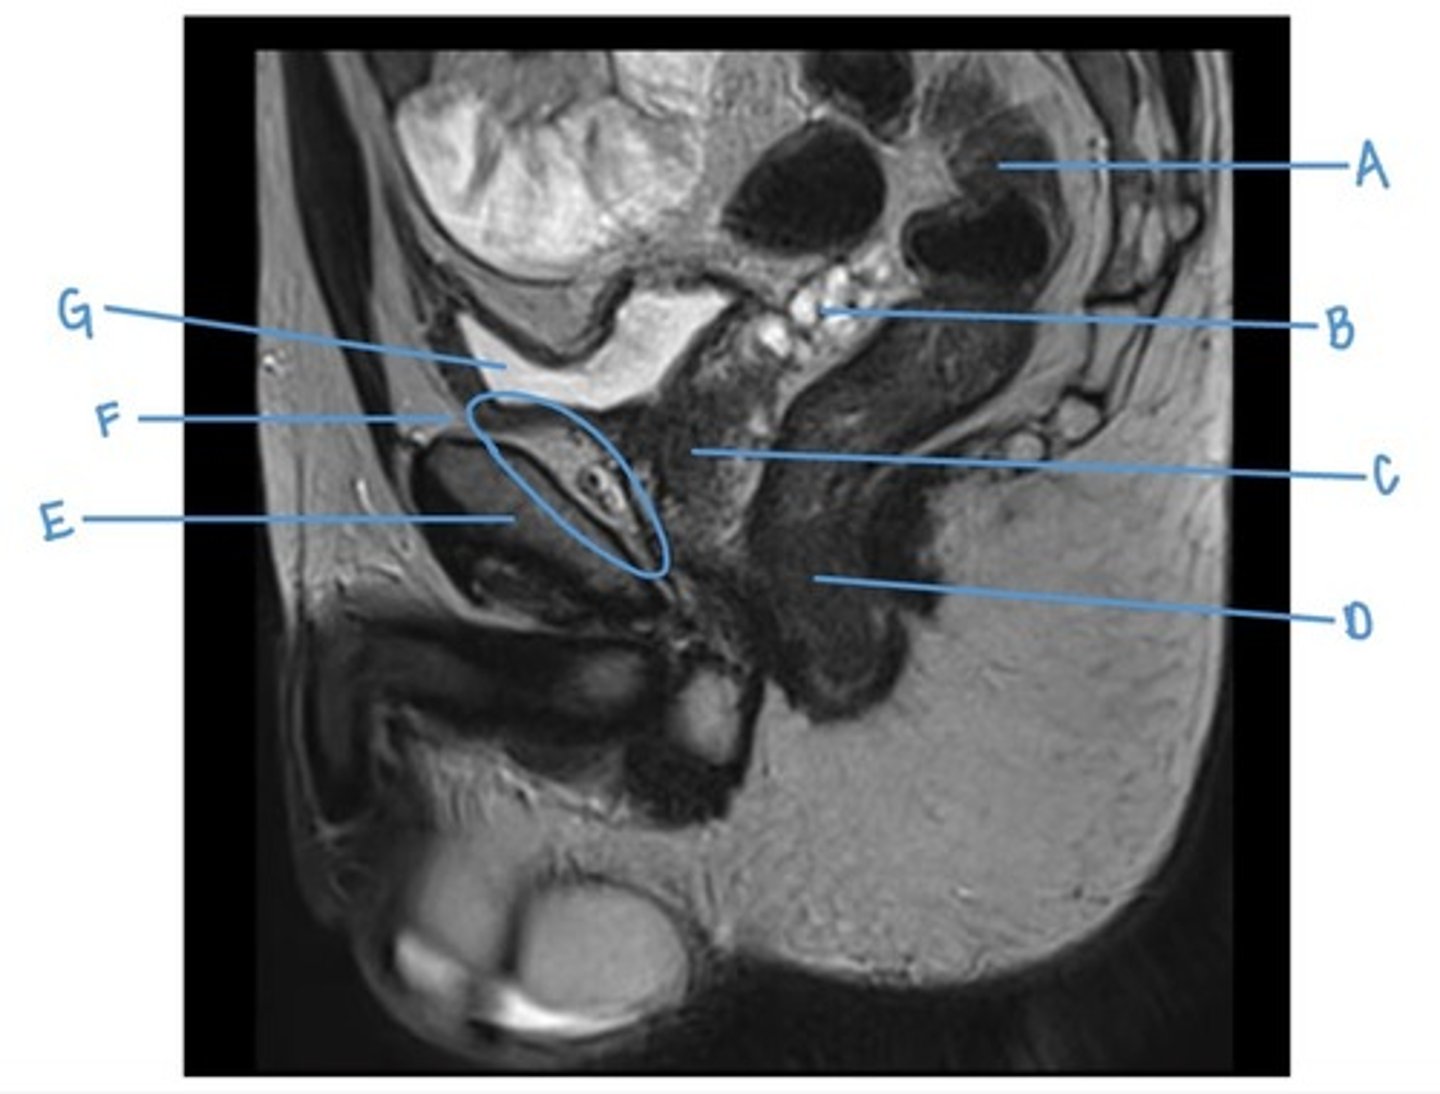

testis

A

pubic symphysis

B

bladder

C

seminal vesicles

D

retro-vesicle pouch

E

rectum

F

sacrum

G

prostate

H

levator ani muscle (pubic diaphragm)

I